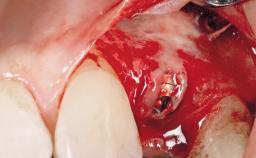

Immediate Placement of an Implant in a Maxillary Left Central Incisor Site

A 33-year-old female patient presented with an upper left central incisor that required extraction after a failed endodontic therapy. The tooth had been traumatized when the patient was a teenager and had undergone several endodontic treatments, including two apicectomy procedures. The patient was in good health and did not smoke. Clinical examination showed that the patient had a high lip line. In full smile, the gingival margins of the upper teeth were visible to the first molars. The gingival margins of central incisors 11 and 21 were only just showing. Examination of tooth 21 confirmed that the tooth was mobile and had hypererupted by 1 mm.

| Placement Protocol | Immediate implant placement |

| Socket Morphology | Single-root socket |

| Socket Integrity | Damage to one or more bone walls |